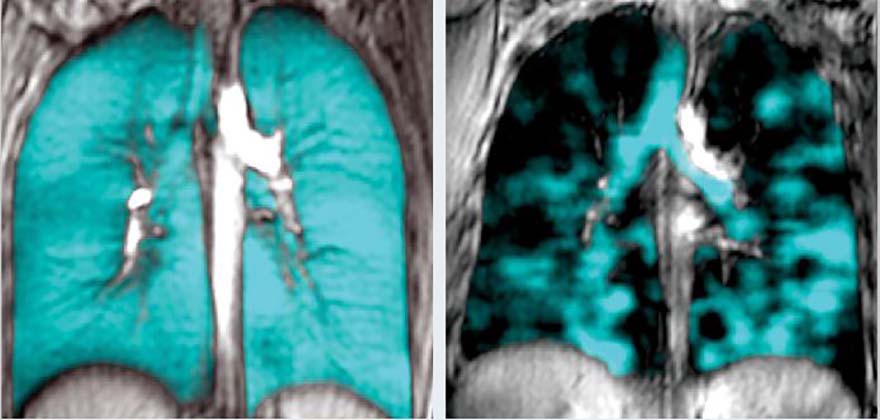

The images side-by-side are strikingly different. The one on the left, a healthy pair of lungs showing blue inhaled gas that fills the lungs completely. The one on the right, the lungs of a young person who vaped for a few months and became severely ill. The numerous dark regions show areas in the lungs that are blocked from inhaled air.

Grace Parraga, HBSc’84, MSc’86, PhD, Canada Research Chair in Lung Imaging to Transform Outcomes and Professor in Medical Biophysics has generated and examined the images of thousands of lungs in the past decade and never before has she seen anything like this.

“We are seeing a lot of patchiness in the lungs of young vapers. We never see this in young healthy lungs,” she said. “The regions of the lung that have markedly abnormal ventilation tell us that when they breathe, air is being choked off from much of the lung, and we now think we know why.”

Using a specialized MRI method in her lab at Robarts Research Institute and using an inert gas that research participants inhale into their lungs, it is easy to see where the gas goes in the lungs, and more importantly, where it doesn’t go when it is blocked by destroyed airways and tissue.

The technique, also allows the team to measure the integrity of the tiny airsacs in the lungs, as well as the tissue lining the airsacs where oxygen and carbon dioxide are normally exchanged.